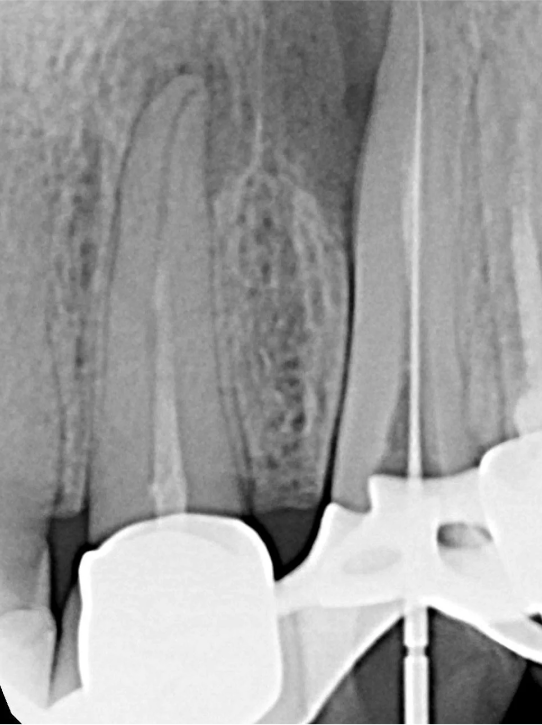

Czy leczenie kanałowe można powtórzyć? Tak, ponowne leczenie endodontyczne (tzw. re-endo) jest możliwe i często konieczne, gdy poprzednie leczenie nie przyniosło oczekiwanych rezultatów lub pojawiły się nowe problemy w danym zębie. W takich sytuacjach precyzja jest jeszcze ważniejsza.

Użycie mikroskopu zabiegowego jest nieocenione, zwłaszcza przy powtórnym leczeniu. Mikroskop pozwala na precyzyjne odnajdywanie dodatkowych kanałów, które mogły zostać pominięte podczas pierwszego leczenia, a także na dokładne opracowanie systemu kanałowego. Dzięki niemu możliwe jest również usuwanie wkładów metalowych czy złamanych narzędzi.

Jednym z wyzwań w leczeniu endodontycznym jest usuwanie złamanych narzędzi z kanałów korzeniowych. To skomplikowana procedura, która wymaga ogromnego doświadczenia i zastosowania mikroskopu, ale w naszym gabinecie podejmujemy się takich wyzwań, aby uratować Twój ząb.

Zarówno ziarniniak okołowierzchołkowy i torbiel zębopochodna uszkadzają struktury okolicznej tkanki kostnej. Podobny proces jeszcze do niedawna był książkowym wskazaniem do interwencji chirurgicznej lub nawet usunięcia zęba. Przy obecnym stanie wiedzy praktycznej wynikającej z doświadczeń pokoleń lekarzy oraz szerokim dostępie do nowoczesnej, specjalistycznej aparatury medycznej, metody terapii stały się mniej inwazyjne, bardziej przewidywalne, mniej radykalne i z założenia prowadzą do zachowania zęba w jamie ustnej.

LECZENIE ENDODONTYCZNE ZE SKOMPLIKOWANĄ ANATOMIĄ ZĘBA